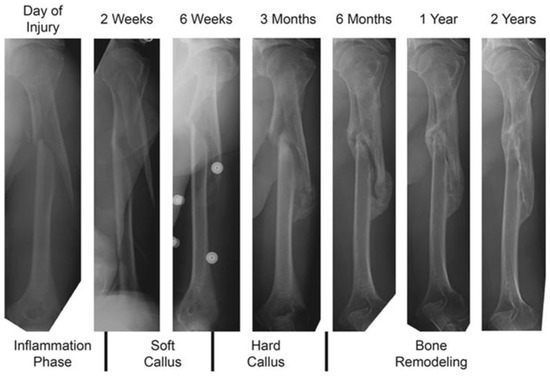

- Doblaré, M.; Garcı́a, J.M.; Gómez, M.J. Modelling bone tissue fracture and healing: A review. Eng. Fract. Mech. 2004, 71, 1809–1840. [Google Scholar] [CrossRef]

- Ghaisi, M.S.; Chen, J.; Vaziri, A.; Rodriguez, E.K.; Nazarian, A. Bone fracture healing in mechanobiological modeling: A review of principles and methods. Bone Rep. 2017, 6, 87–100. [Google Scholar] [CrossRef] [PubMed]